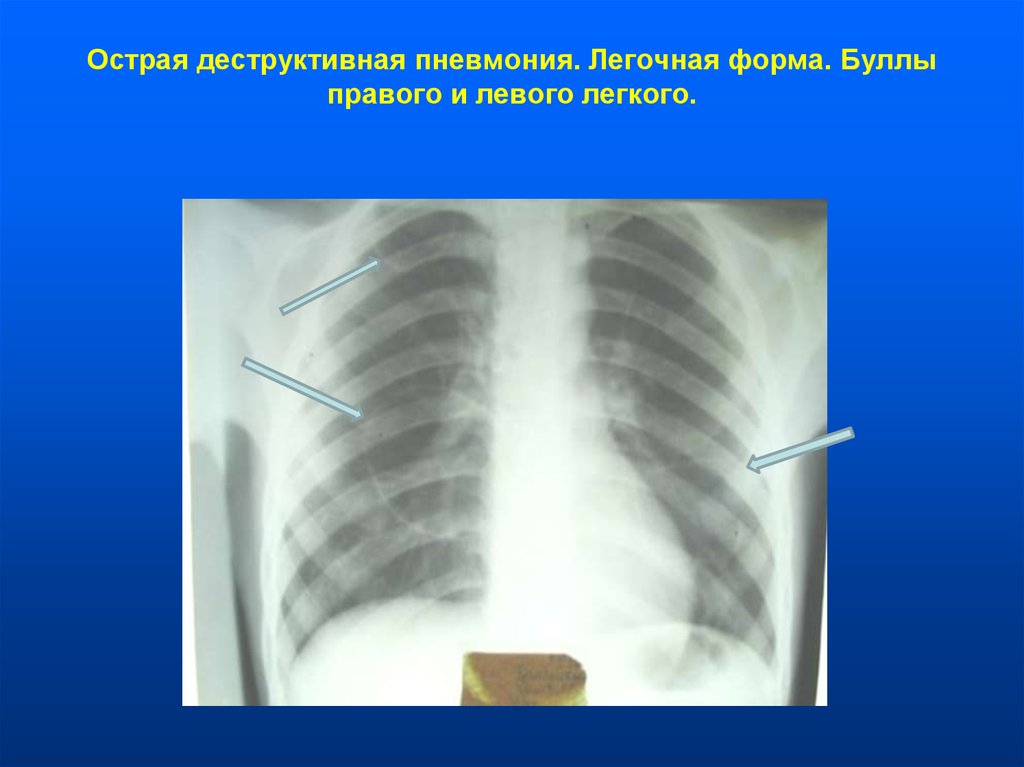

Бактериальная деструкция легких у детей презентация - 88 фото